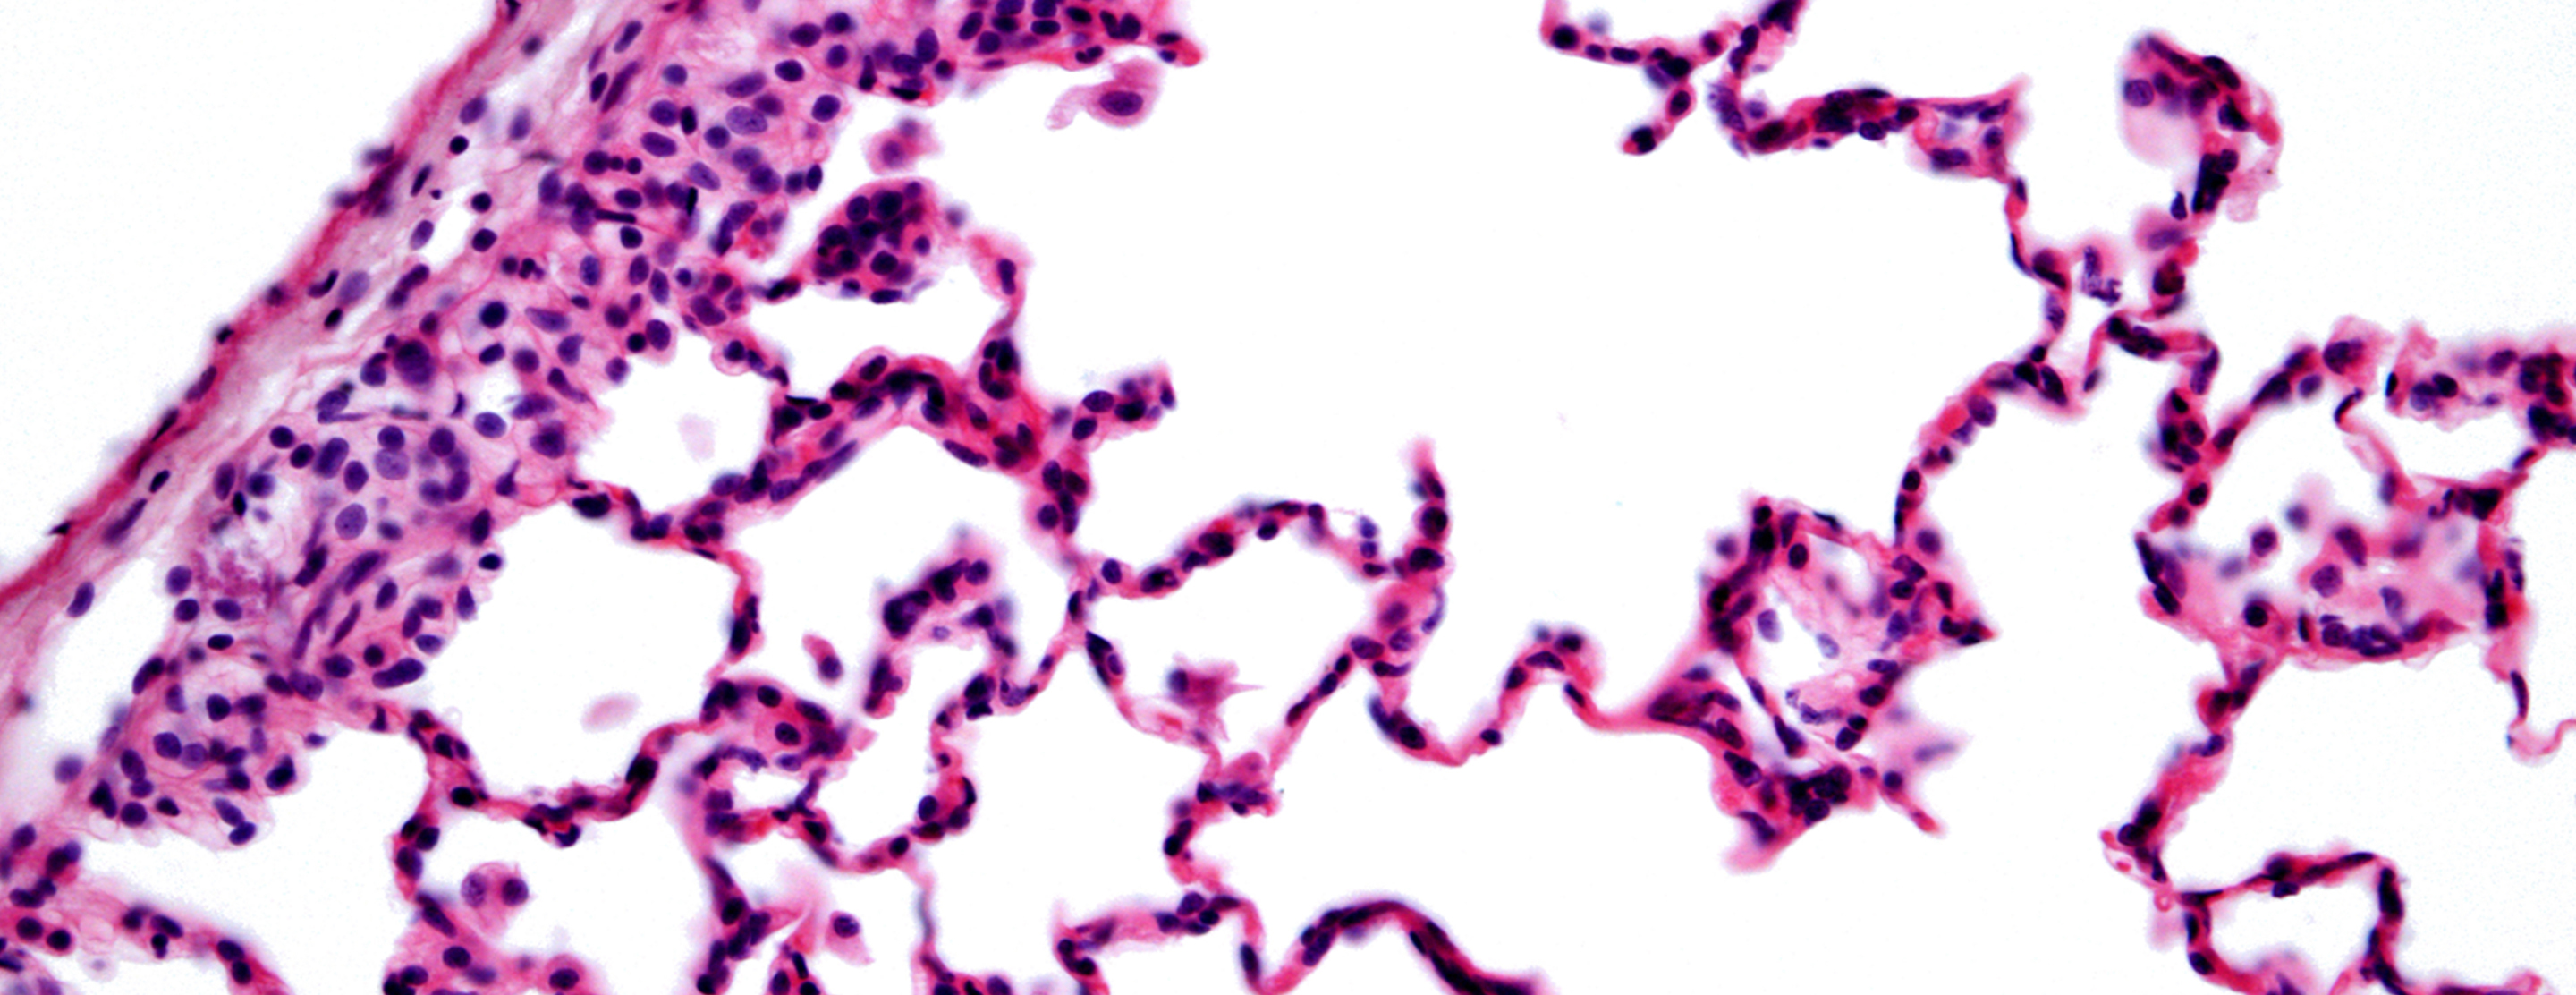

Normal Results

Pleural tissues appear normal, without signs of inflammation, infection, or cancer.